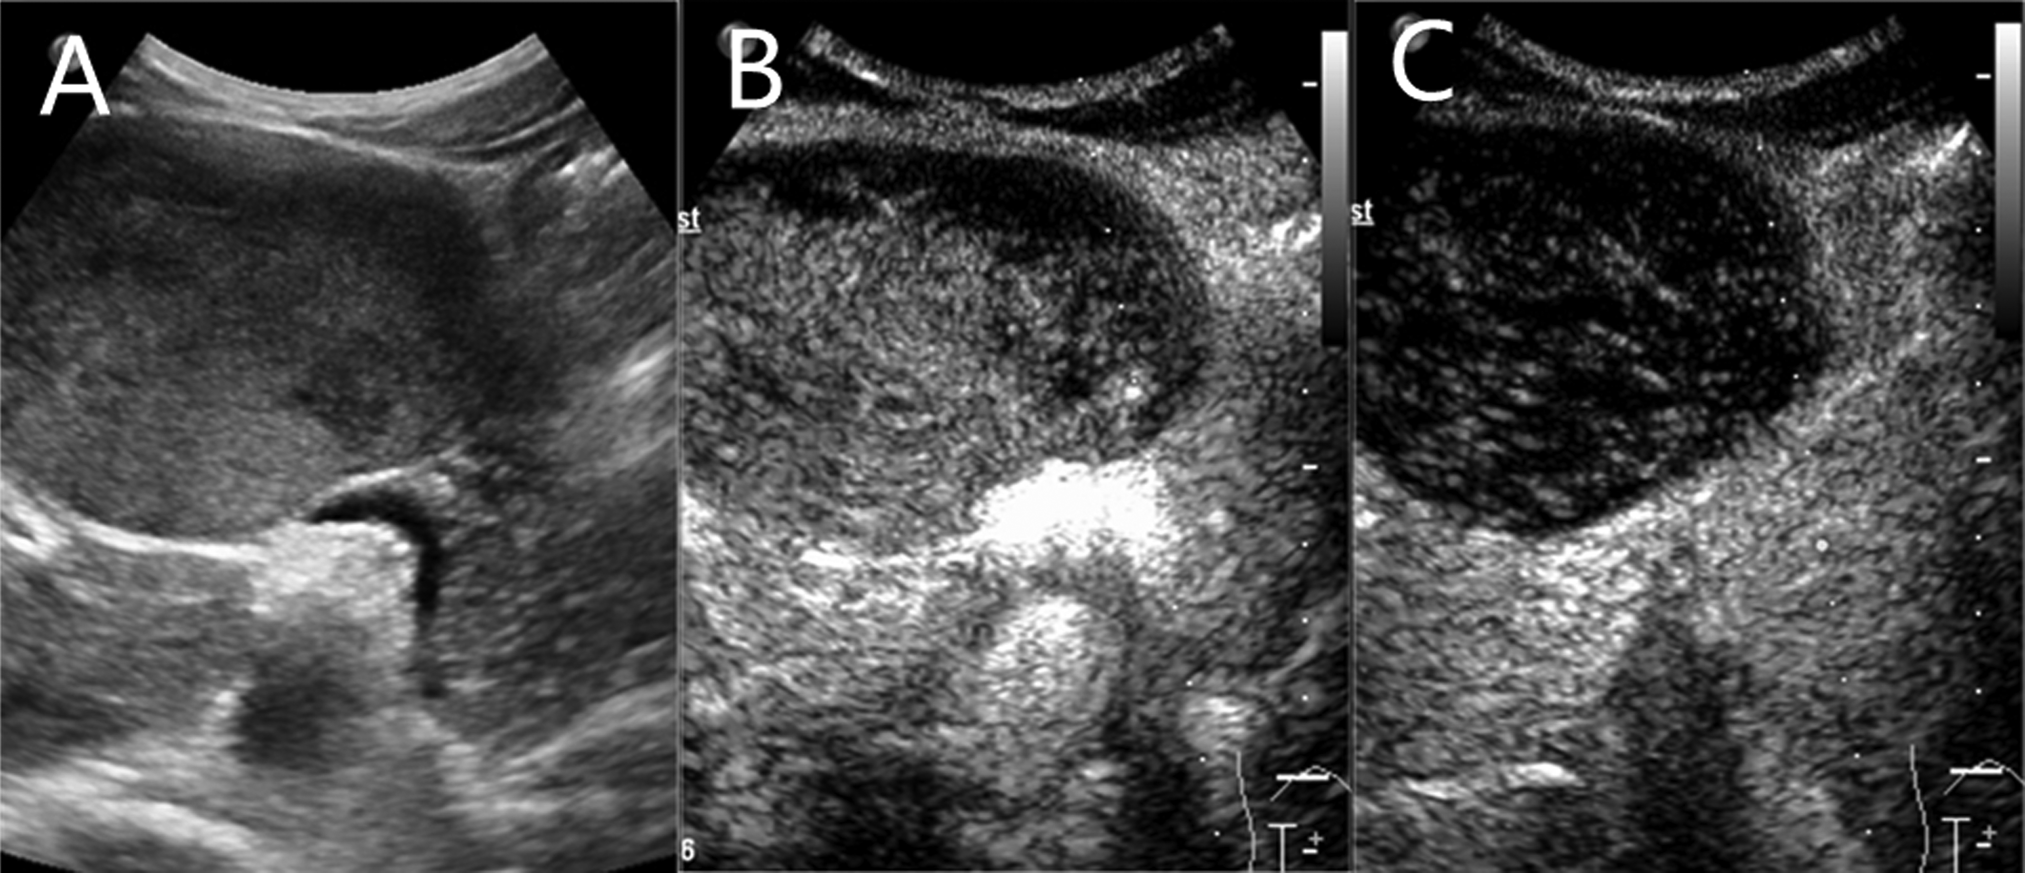

Contrast-enhanced magnetic resonance (MR) revealed an 8.2 × 5.7 cm circular confounding signal mass on the pancreatic neck (Figure 1). It had a slightly higher T1 signal and equal T2 signal with a small patch of high T2 signal inside. Contrast enhancement was heterogeneous high enhancement. The adjacent common hepatic artery and splenic artery were pushed, causing their lumens to narrow slightly, and their local boundaries with the tumor were not clear. The fat space between the splenic vein and the tumor is not clear. The main pancreatic duct and bile duct were not dilated. MR finally considered pancreatic malignant cystadenoma or solid pseudopapillary tumor (SPT). Two-dimensional ultrasonography revealed a slightly weaker echogenic mass of approximately 8.6 × 6.4 cm in the pancreatic neck body area, with clear boundaries, clear capsules, heterogeneous internal echoes, and small hypoechoic areas (Figure 2A). CEUS showed rapid and high enhancement at the margin and equal enhancement at the interior of the mass in the arterial phase. In the parenchymal phase, the overall enhancement was low. CEUS considered mostly SPT (Figures 2B,C).

Figure 2

A slightly weaker echogenic mass on ultrasound. (A) Two-dimensional ultrasonography. (B) contrast-enhanced ultrasound (CEUS) in arterial phase. (C) CEUS in parenchymal phase.